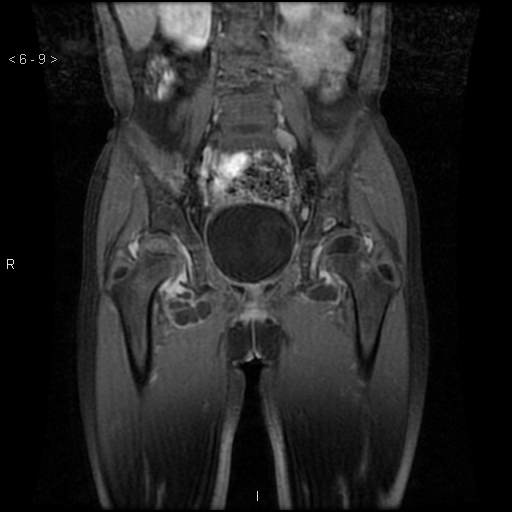

| 第201412期儿研所病例讨论之四 女孩,7岁。双髋关节疼痛2年余,关节活动受限近1年。      诊断:幼年特发性关节炎伴米粒体形成。 【儿研所 点评】 长期的滑膜炎症时,关节内可以出现边界清楚的游离结节,称为“米粒体”。 组织学上,米粒体中心为嗜酸性无定形组织,外围为胶原及纤维成分。多数学者认为其继发于滑膜小梗死灶,致使滑膜脱落,由滑液中的纤维蛋白包裹而成。 MR图像中,米粒体由于其本身的纤维组成,且周围是关节液和增生的滑膜,所以在T2WI中表现为高信号关节内的低信号,在增强扫描图像中滑膜强化信号升高,米粒体仍为低信号。 米粒体无特异性,多继发于幼年特发性关节炎等慢性滑膜炎。在幼年特发性关节炎患者中,米粒体可发生于病程的早期或晚期,主要见于膝关节,与病程、临床表现和严重程度及影像学改变无明确关系。 |